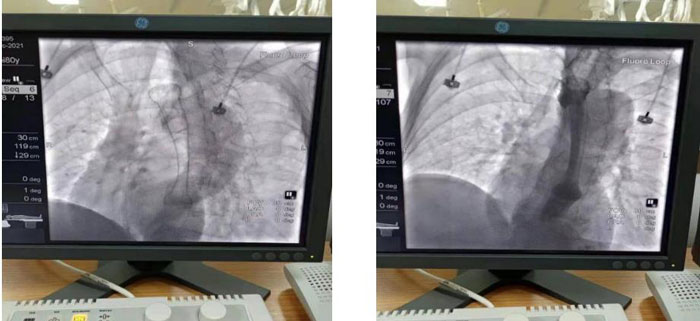

患者于2021年12月15日行“食管球囊擴(kuò)張+食管支架植入術(shù)”。術(shù)中在數(shù)字減影X光機(jī)透視下準(zhǔn)確定位示狹窄位于食管胸中段,長(zhǎng)約6CM,管腔極度狹窄,僅少量造影劑呈線型通過(guò),鉛標(biāo)標(biāo)記狹窄遠(yuǎn)近兩端;導(dǎo)絲引導(dǎo)下經(jīng)口、食道引入5f造影導(dǎo)管至胃內(nèi),造影確認(rèn)導(dǎo)管位于胃內(nèi),退出導(dǎo)管保留導(dǎo)絲,沿導(dǎo)絲引入球囊擴(kuò)張導(dǎo)管擴(kuò)張食管狹窄段。退出球囊保留導(dǎo)絲, 沿導(dǎo)絲將18mm*100mm型號(hào)食道支架放置于食管狹窄處,確認(rèn)位置合適后釋放推送器使支架擴(kuò)張,支架擴(kuò)張后退出推送器及導(dǎo)絲;再次口服造影劑可見(jiàn)食管全段通暢,支架擴(kuò)張良好,手術(shù)順利完成。

術(shù)中食管球囊擴(kuò)張狹窄段,以利于支架植入

支架植入順利,造影示支架植入位置良好食管全程通暢